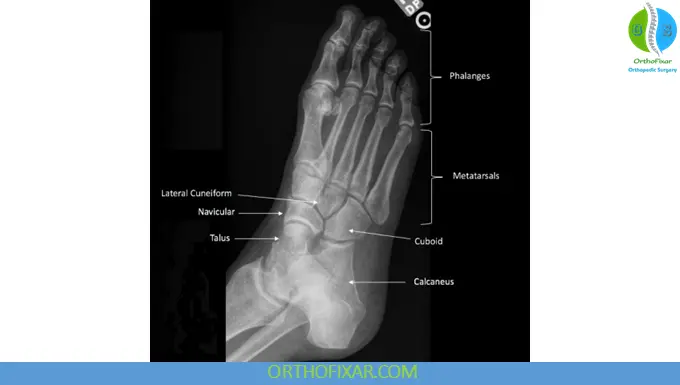

Anatomy Overview Relevant to Foot X-Ray

The foot consists of:

- Hindfoot: Talus and calcaneus

- Midfoot: Navicular, cuboid, and three cuneiform bones

- Forefoot: Metatarsals and phalanges

2. Oblique View of the Foot (Medial Oblique)

Positioning

- The foot is rotated medially approximately 30–45°

- The plantar surface remains in contact with the receptor

Structures Best Visualized

- Cuboid and navicular bones

- Calcaneocuboid joint

- Intermetatarsal spaces